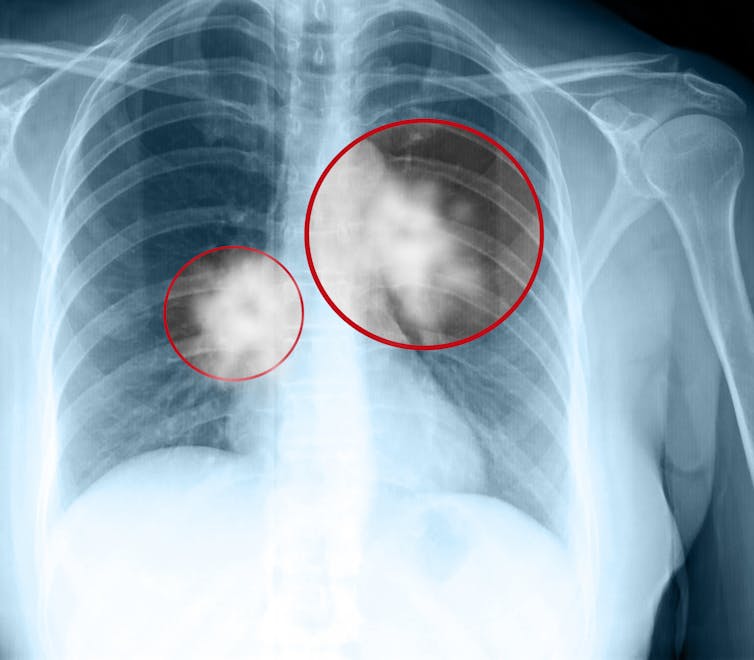

Since the 1960s, lung cancer has been (by far) the world’s leading cause of cancer death. Lung cancer (almost all of which can be attributed to smoking) was responsible for 18% of all cancer deaths in 2020, with the next most frequent killer, liver cancer, at 8.3%.

There is a great deal of early evidence now available that vaping is likely to be anything but benign. For example, recent reviews on vapes have found they contain carcinogens known to cause lung cancer, are correlated with asthma, and impair our vascular systems.